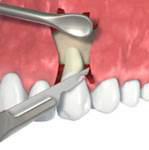

Tyto postupy nám umožní doplnit chybějící množství kosti v čelistech pacienta i zlepšit kvalitu kosti. Většinou se setkáváme s omezenou nabídkou kostní tkáně díky resorpčním (úbytkovým) procesům způsobených věkem či vytržením zubu, přítomností anatomických struktur jako je čelistní dutina, nervový kanál nebo patologických či poúrazových stavů - cysty, zlomeniny.

Při ztrátě molárů a premolárů v horní čelisti a jejich náhradě implantáty se často setkáváme s nedostatečnou

vertikální nabídkou kosti pod čelistní dutinou, často doprovázenou i nedostatečnou horizontální nabídkou a sníženou kvalitou kosti (v oblasti 2. premoláru v 50%, v oblasti moláru až v 80% případů nedostatečná kostní nabídka)